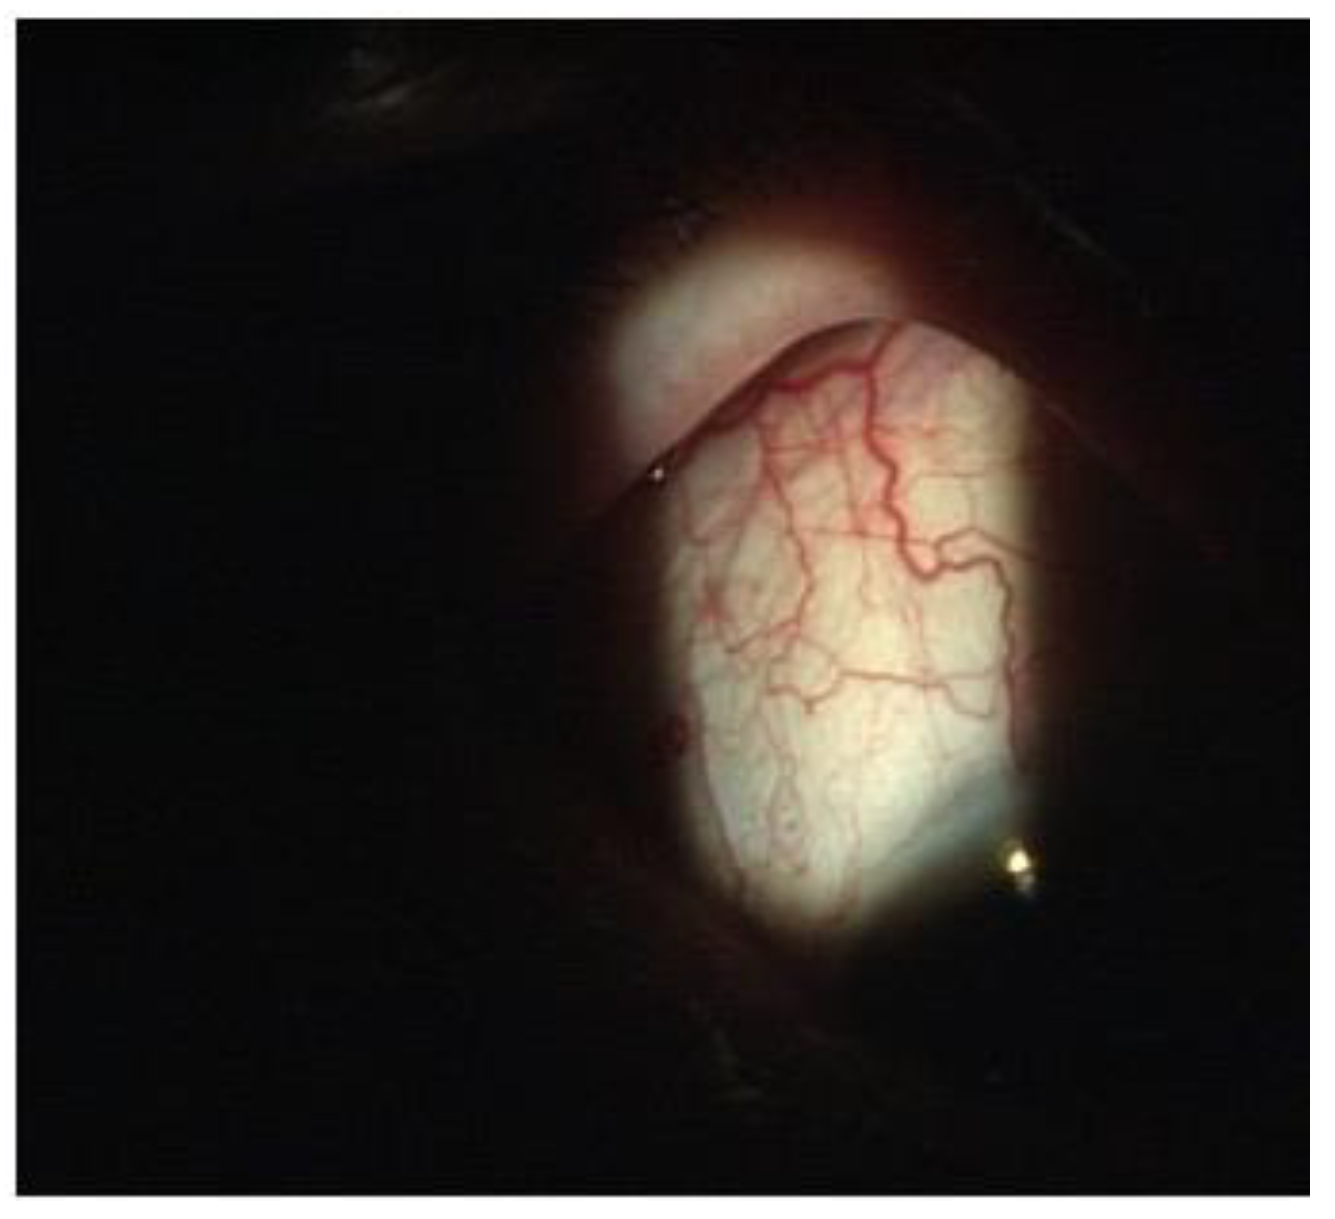

A 65-year-old woman presented to our attention complaining of two days of swelling in the right eye, reduced visual acuity, diplopia, and mild pain. The history was negative for recent trauma and confirmed good general health conditions. The physical examination revealed complete ophthalmoplegia (Figure 1), non-pulsatile reducible axile exophthalmos, eyelid edema, significant chemosis, and conjunctival ectropion (Figure 2). Visual acuity at the time of admission was 5/10 in the right eye and 10/10 in the left eye. The biomicroscopic examination of the anterior segment showed an important stasis of the episcleral vessels (Figure 3) and a shallow anterior chamber, whereas the fellow eye was unremarkable.

On the third post-operative day, the clinical condition was significantly improved in the following ways: a clear reduction of the exophthalmos and the congestion of the episcleral vessels (Figure 7), a complete recovery of ocular motility (Figure 8), visual acuity improved to 10/10, IOP was 14 mmHg, the disappearance of cotton exudates, and a normalization of the A/V ratio. Fifteen days after the surgery, the ocular conditions were stable.

Figure 7. Resolution of the dilatation of the episcleral vessels, exophthalmos, and ophthalmoplegia.